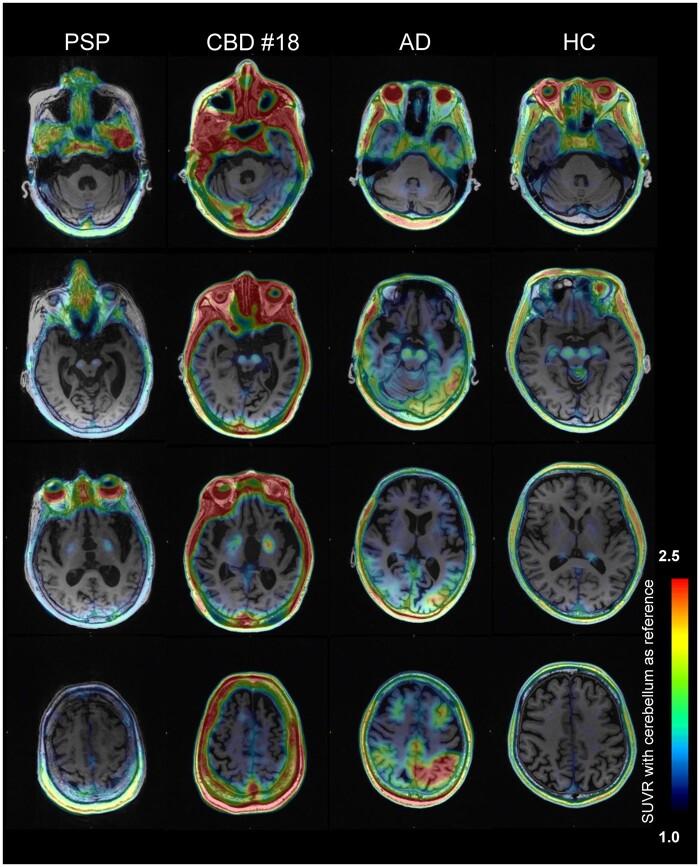

Tau aggregates represent a key pathologic feature of Alzheimer's disease and other neurodegenerative diseases. Recently, PET probes have been developed for detection of tau accumulation; however, they are limited because of off-target binding and a reduced ability to detect tau in non-Alzheimer's disease tauopathies. The novel tau PET tracer, [F]PI-2620, has a high binding affinity and specificity for aggregated tau; therefore, it was hypothesized to have desirable properties for the visualization of tau accumulation in Alzheimer's disease and non-Alzheimer's disease tauopathies. To assess the ability of [F]PI-2620 to detect regional tau burden in non-Alzheimer's disease tauopathies compared with Alzheimer's disease, patients with progressive supranuclear palsy ( = 3), corticobasal syndrome ( = 2), corticobasal degeneration ( = 1) or Alzheimer's disease ( = 8), and healthy controls ( = 7) were recruited. All participants underwent MRI, amyloid β assessment and [F]PI-2620 PET (Image acquisition at 60-90 min post-injection). Cortical and subcortical tau accumulations were assessed by calculating standardized uptake value ratios using [F]PI-2620 PET. For pathologic validation, tau pathology was assessed using tau immunohistochemistry and compared with [F]PI-2620 retention in an autopsied case of corticobasal degeneration. In Alzheimer's disease, focal retention of [F]PI-2620 was evident in the temporal and parietal lobes, precuneus, and cingulate cortex. Standardized uptake value ratio analyses revealed that patients with non-Alzheimer's disease tauopathies had elevated [F]PI-2620 uptake only in the globus pallidus, as compared to patients with Alzheimer's disease, but not healthy controls. A head-to-head comparison of [F]PI-2620 and [F]PM-PBB3, another tau PET probe for possibly visualizing the four-repeat tau pathogenesis in non-Alzheimer's disease, revealed different retention patterns in one subject with progressive supranuclear palsy. Imaging-pathology correlation analysis of the autopsied patient with corticobasal degeneration revealed no significant correlation between [F]PI-2620 retention . High [F]PI-2620 uptake at 60-90 min post-injection in the globus pallidus may be a sign of neurodegeneration in four-repeat tauopathy, but not necessarily practical for diagnosis of non-Alzheimer's disease tauopathies. Collectively, this tracer is a promising tool to detect Alzheimer's disease-tau aggregation. However, late acquisition PET images of [F]PI-2620 may have limited utility for reliable detection of four-repeat tauopathy because of lack of correlation between post-mortem tau pathology and different retention pattern than the non-Alzheimer's disease-detectable tau radiotracer, [F]PM-PBB3. A recent study reported that [F]PI-2620 tracer kinetics curves in four-repeat tauopathies peak earlier (within 30 min) than Alzheimer's disease; therefore, further studies are needed to determine appropriate PET acquisition times that depend on the respective interest regions and diseases.